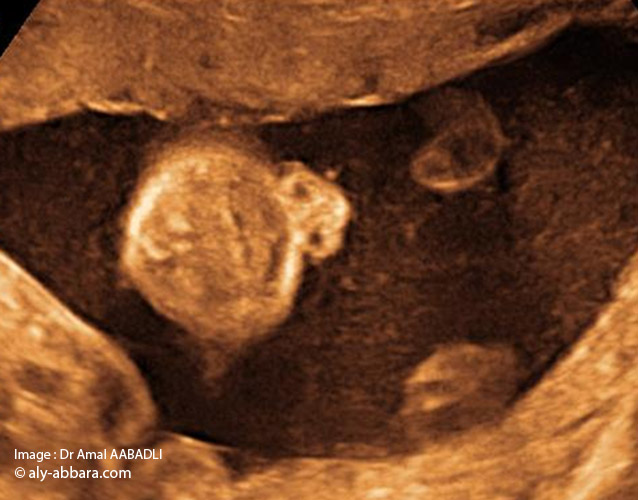

Coupe frontale de face : nez, bouche et menton_01

صورة الأنف الفم و الذقن

لا يكون إتمام فحص جنين ما دون فحص منطقة الأنف و الفم و الذقنً

يتم الحصول على هذه الصورة بقطعة تاجية للوجه و هذا يعني أن المسبار الصدوي يجب أن يوضع من الجبهة إلى الأسفل – نقول أيضاً قطعة جبهية و المعنى واحد- كأنه تاج. و يمكن أيضاً أن نوجهه من أسفل الذقن

هدف هذه الصورة هو التأكد من عدم وجود عَلَم شفهي

• La coupe échographique fœtale " nez, bouche et menton :

• L'étude morphologique du fœtus ne peut être complète sans l'examen de la région du "nez, bouche et menton".

• Pour obtenir cette image il faut effectuer une coupe coronale (frontale) sur la face, pour cela il faut diriger la sonde échographique posée sur le front du fœtus vers le bas du visage ; ou l'inverse, diriger la sonde posée sur le menton vers le haut du visage.

• Le but de cette image est de s'assurer de l'absence de fente labiale (bec de lièvre).